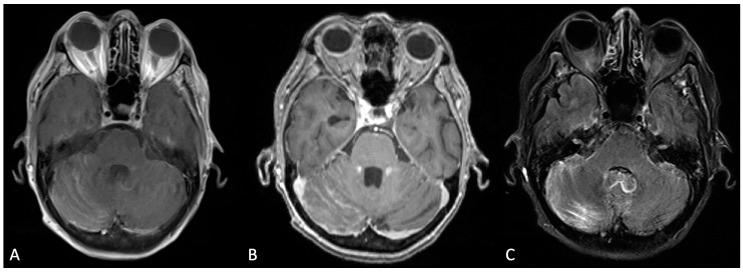

The present review aimed to establish an understanding of the pathophysiology of leptomeningeal disease as it relates to late-stage development among different cancer types. For our purposes, the focused metastatic malignancies include breast cancer, lung cancer, melanoma, primary central nervous system tumors, and hematologic cancers (lymphoma, leukemia, and multiple myeloma). Of note, our discussion was limited to cancer-specific leptomeningeal metastases secondary to the aforementioned primary cancers. LMD mechanisms secondary to non-cancerous pathologies, such as infection or inflammation of the leptomeningeal layer, were excluded from our scope of review. Furthermore, we intended to characterize general leptomeningeal disease, including the specific anatomical infiltration process/area, CSF dissemination, manifesting clinical symptoms in patients afflicted with the disease, detection mechanisms, imaging modalities, and treatment therapies (both preclinical and clinical). Of these parameters, leptomeningeal disease across different primary cancers shares several features. Pathophysiology regarding the development of CNS involvement within the mentioned cancer subtypes is similar in nature and progression of disease. Consequently, detection of leptomeningeal disease, regardless of cancer type, employs several of the same techniques. Cerebrospinal fluid analysis in combination with varied imaging (CT, MRI, and PET-CT) has been noted in the current literature as the gold standard in the diagnosis of leptomeningeal metastasis. Treatment options for the disease are both varied and currently in development, given the rarity of these cases. Our review details the differences in leptomeningeal disease as they pertain through the lens of several different cancer subtypes in an effort to highlight the current state of targeted therapy, the potential shortcomings in treatment, and the direction of preclinical and clinical treatments in the future. As there is a lack of comprehensive reviews that seek to characterize leptomeningeal metastasis from various solid and hematologic cancers altogether, the authors intended to highlight not only the overlapping mechanisms but also the distinct patterning of disease detection and progression as a means to uniquely treat each metastasis type. The scarcity of LMD cases poses a barrier to more robust evaluations of this pathology. However, as treatments for primary cancers have improved over time, so has the incidence of LMD. The increase in diagnosed cases only represents a small fraction of LMD-afflicted patients. More often than not, LMD is determined upon autopsy. The motivation behind this review stems from the increased capacity to study LMD in spite of scarcity or poor patient prognosis. In vitro analysis of leptomeningeal cancer cells has allowed researchers to approach this disease at the level of cancer subtypes and markers. We ultimately hope to facilitate the clinical translation of LMD research through our discourse.